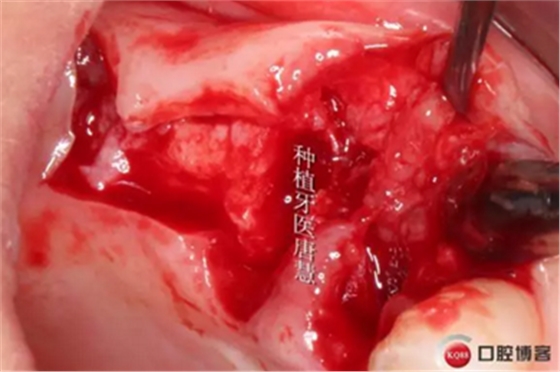

翻瓣,肉芽超多

15根尖區(qū)大塊肉芽腫

大量鹽水沖洗后